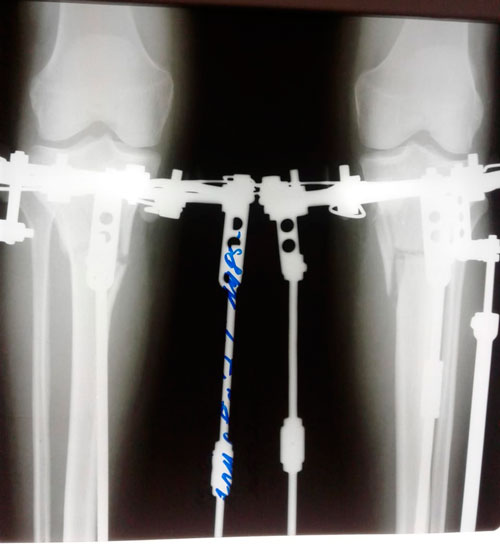

перед крутками

IMG_2072-27-03-19-01-18.gif

IMG_2073-27-03-19-01-18.gif